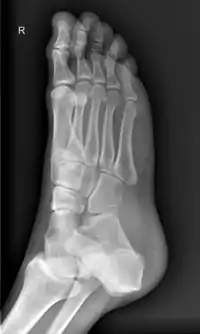

足,又称腳、跤,解剖学上指陸地脊椎動物腿的末端、支撑该生物的部分。大多数双足及许多四足动物的脚有以下结构:踝关节,脚跟,足弓,脚趾。脚是人和某些脊椎动物肢体的末端接触地面的部分,是人体的负重器官和运动器官。在许多有脚的生物中,脚是腿末端的独立器官,由一个或多个部分或骨骼组成,通常包含爪子和趾甲。

在解剖学上,足部的定义位置是位于踝部远侧,分为足背、足底和足趾。而足底(跖)涵盖了跖丘(ball of the foot,足趾和足弓之间)、足弓、足跟;足趾再细分趾根、趾身、趾端、趾甲等部位[1]。但在口语中,人类的“脚”可能较广义,可包含足踝,甚至腿部。

脚的构造分三个部分,即前、中、后脚部。这三个分布的构造及功能都不一样。[2]

| 双足骨骼 | 共52块(全身骨骼的六分之一) | 组成足部结构 、关节的钙质等物质的代谢等调节 |

| 双足关节 | 共66个 | 局部各种活动 , 富有弹性等功能 |

| 双足韧带 | 共214条 | 使各关节易于联络活动 , 协调及缓冲压力 |

| 双足肌肉 | 共38条(全身肌肉的43%) | 舒张及收缩之运动功能 , 具有冲击力 |

| 足弓 | 纵弓高度:男性4.74厘米,女性3.13厘米 | 富有弹性 , 缓冲重力 , 减轻震荡 , 保护关节 |